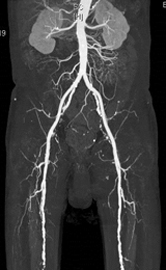

CT検査は体内における各臓器、組織のX線透過量の違いをデータとして収集し、コンピュータで断面像にしています。また、この断面像を細かく収集し積み重ねて画像処理をすることにより、任意の角度から観察することが出来るMPR画像や、3D構築画像を得ることも出来ます。さらに造影剤を使用することによって、血管の3D画像も容易に得ることが出来ます。